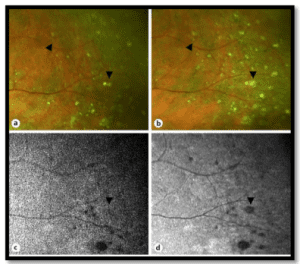

En el estudio Koronyo et al, como puede observarse en la Figura 9, la retina de pacientes con EA contiene gran cantidad de depósitos de Aβ, especialmente en la capa de células ganglionares (CGL). La pérdida marcada de células retinianas es evidente en el CGL, la capa nuclear interna (INL) y la capa nuclear externa (ONL). La membrana limitante interna (ILM) y la capa de fibra nerviosa retiniana (RNFL) están intactas en CTRL en contraste con EA. Imágenes de mayor aumento muestran depósitos de Aβ cerca y dentro de las paredes de los vasos sanguíneos y dentro del soma de células ganglionares. Se tomaron imágenes de las retinas de los sujetos con un oftalmoscopio de escaneo láser modificado antes y después de la ingesta de curcumina. Las manchas blancas marcadas con círculos rojos son placas amiloides positivas para la curcumina detectadas en la retina de un paciente con EA.

Figura 9. Imagen retiniana no invasiva en pacientes con Alzheimer: detección de depósitos de Aβ y degeneración nerviosa a través de la oftalmoscopia con escáner láser y la tomografía de coherencia óptica. (A, B) Secciones transversales de la retina de cuadrantes superiores de pacientes con enfermedad de Alzheimer.